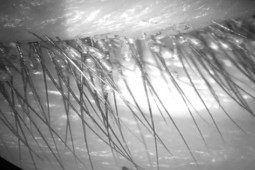

Hình ảnh rận ký sinh chi chít ở nách người đàn ông ở Nghệ An

Qua thăm khám, bệnh nhân được chỉ định xét nghiệm tìm ký sinh trùng trên cơ thể (nạo, soi da và lông nách dưới kính hiển vi). Kết quả, phát hiện nhiều trứng rận bám chắc trên lông, ấu trùng rận, rận trưởng thành bám chắc vào da vùng nách của bệnh nhân.